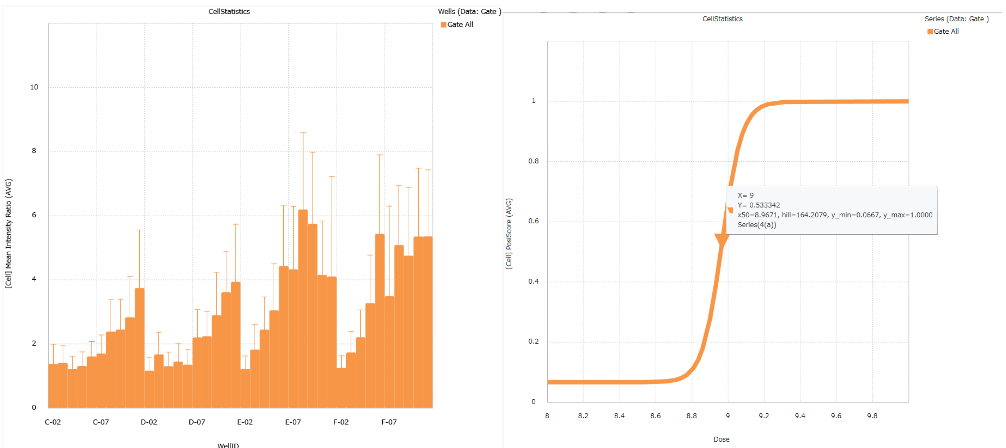

EC50/IC50 calculation (deep image response)

Image Credit: Yokogawa Life Science

Using whole images, this function allows for the thorough quantification of complicated phenotypes. Simple process of entering compound concentration data and choosing positive and negative wells. There is no need for any process to segment cells.

Convenient graphing tools

Image Credit: Yokogawa Life Science

The analysis findings can be shown as a bar chart, line chart, pie chart, scatter plot, heatmap, or histogram. The results can also be estimated using the EC50, IC50, and Z'-factor.

EC50/IC50 calculation (deep image response)

Image Credit: Yokogawa Life Science

This feature makes it possible to use whole images to measure complicated phenotypes thoroughly. Choosing positive and negative wells and entering information regarding compound concentration is simple. Segmentation of cells does not require any methodology.

Improved EC50 calculation

Convenient graphing tools

Image Credit: Yokogawa Life Science

An analysis's findings can be shown using a histogram, bar chart, scatter plot, pie chart, heatmap, and bar chart. The results can also be estimated using the EC50, IC50, and Z'-Factor.